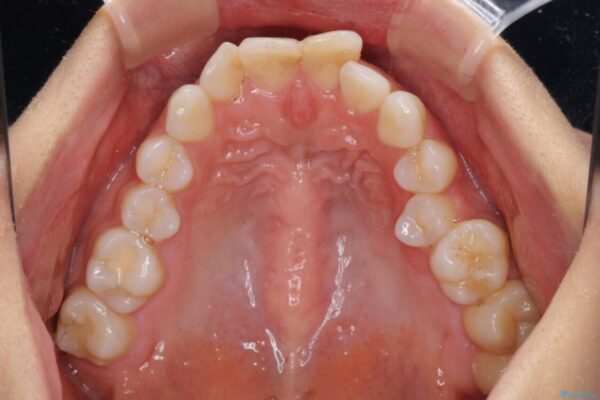

治療後

• 【モニター】出っ歯と咬み合わせを改善 ワイヤー装置の抜歯矯正 治療後画像